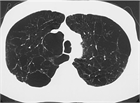

病態

1. 慢性閉塞性肺疾患(chronic obstructive pulmonary disease:COPD)は、タバコ煙を主とする有害物質を長期に吸入曝露することで生ずる肺の炎症性疾患であり、呼吸機能検査で正常に復することのない気流閉塞を示す。